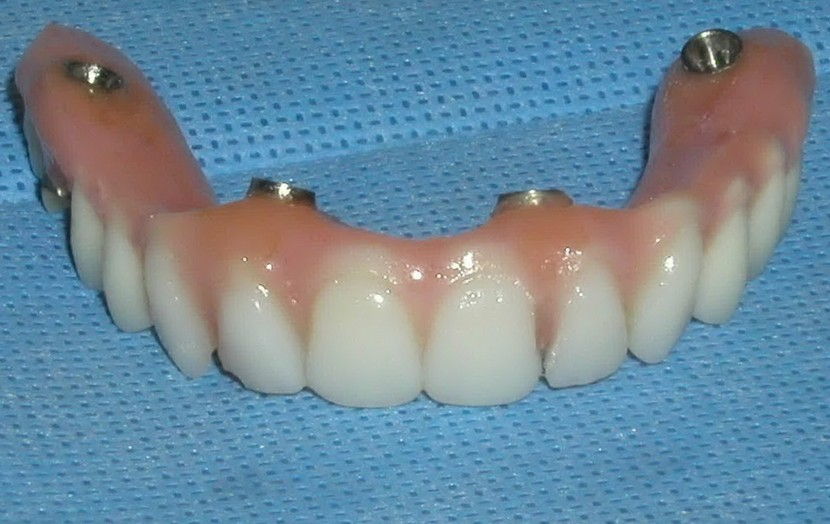

Nakon ugradnje implantata potrebno je vrijeme da bi se on integrirao, odnosno srastao sa kosti. Taj proces se naziva osteointegracija, a traje između 4 do 6 mjeseci. Kad u čeljusti uopće nemamo zubi možemo ih staviti u obliku fiksnog mosta na samo 4 implantata. To se zove sistem ALL-ON-FOUR.